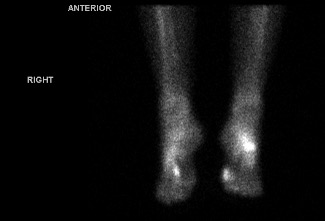

Finally, things made sense. One targeted MRI still showed nothing, but a nuclear bone scan lit up both feet—proof that my pain was real. The weight of being dismissed for years was finally lifted!